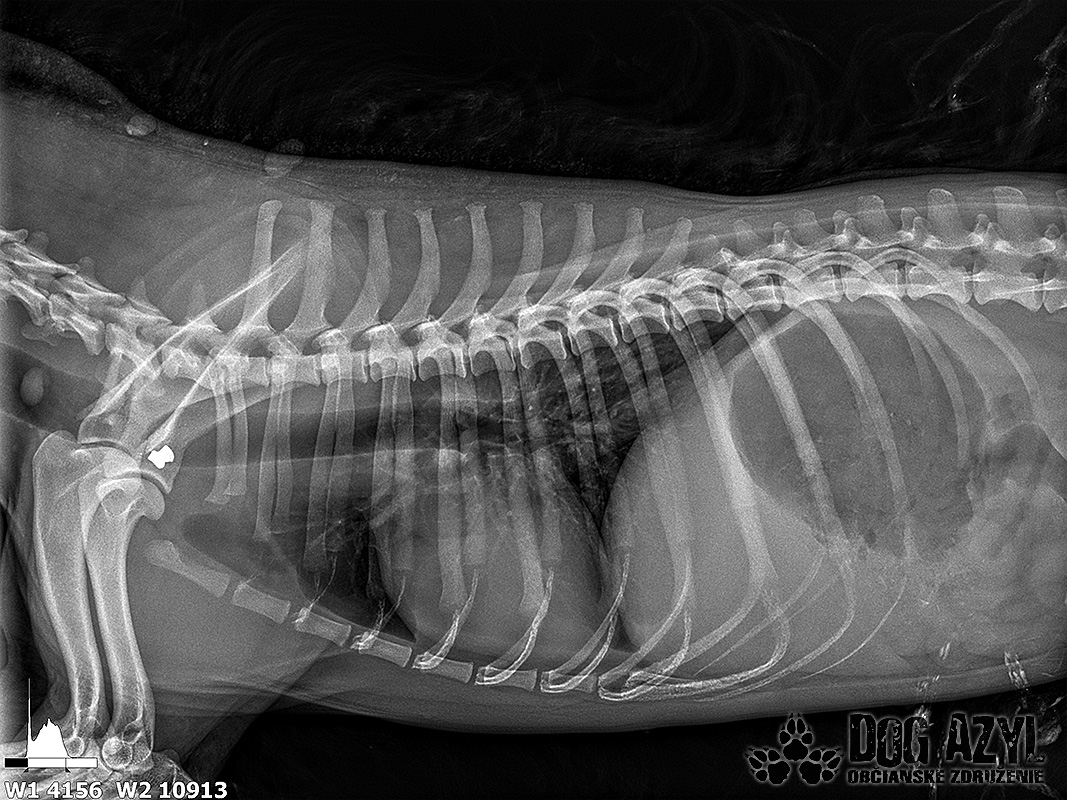

Vianoce nám klopú na dvere a mali by to byť sviatky radosti a pokoja. No u nás nebudú a pre malého Jamesa už vôbec nie. Malého Jamesa sme prijali s mnohonásobnými fraktúrami panvy. Presnejšie, s obojstrannou iliosakrálnou luxáciou/fraktúrou, viacnásobnou fraktúrou panvy, vrátane fraktúry kranialneho acetabula obojstranne. Áno, znie to hrozivo a keď si pozriete snímky z RTG, bude to ešte hrozivejšie (ďalšie snímky ešte doplníme).

Čakali ho teda štyri, veľmi náročné ortopedické operácie, takže sa musel trocha posilniť. Do starostlivosti si ho vzala MVDr. Panyi Terzieva a 17.11. mohol absolvovať prvú operáciu. V "prvom kole" krpec zvládal anestézu tak dobre, že sa rovno mohli spojiť dve operácie a tak sa celá ľavá strana dala do poriadku. Zostal samozrejme naďalej hospitalizovaný. Ďalší zákrok sa naplánoval na 20.11. a našťastie opäť všetko prebehlo hladko, a zoperovala sa celá pravá strana(nechceme sa dlho rozpisovať, prikladáme lekársku správu). James bol prepustený 24.11. ako chodiaci pacient a bez problémov ovládal aj vylučovanie! Je to priam zázrak, za ktorý opäť vďačíme MVDr. Vatolíkovi a jeho teamu.